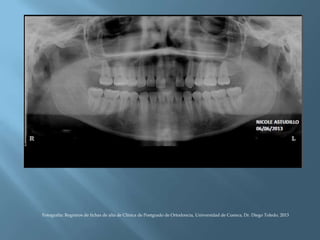

Fotografía: Registros de fichas de alta de Clínica de Postgrado de Ortodoncia, Universidad de Cuenca, Dr. Diego Toledo, 2013.

Elaborar el

los espacios

FINAL: constatar

RX

Fotografía: Registros de fichas de alta de Clínica de Postgrado de Ortodoncia, Universidad de Cuenca, Dr. Diego Toledo, 2013